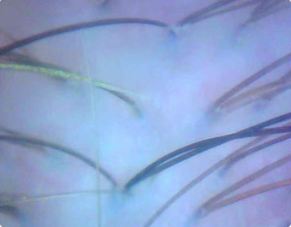

Изображения кератина кожи головы при 60-кратном увеличении, до нанесения и после 28 дней регулярного использования.

До нанесения.

После 28 дней регулярного использования.